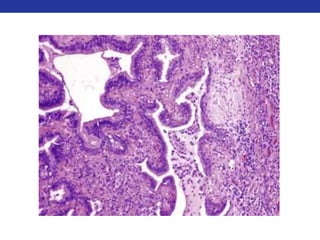

• Histology:

• Edema and cellular infiltrates within the bronchial wall

• “Fragile” appearance of the epithelium and detachment of epithelial cells

• Hypertrophy and hyperplasia of the smooth muscle layer

• Increased deposition of collagen (basement membrane thickening) = fibrosis.

• Hypertrophy of mucous glands